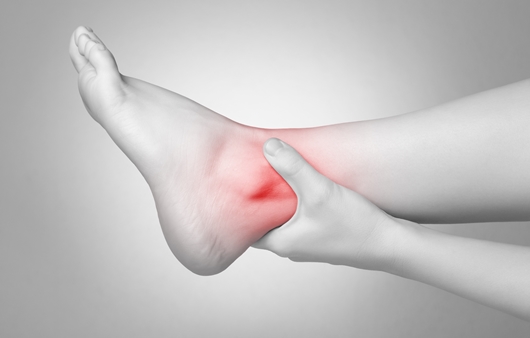

통풍은 요산이 체내에 쌓여 혈액 속 요산 농도가 높아져 관절에 달라붙어 통증을 유발합니다. 유전적인 요인도 있지만 대부분 비만, 과음, 스트레스 등 복합적인 요소로도 나타날 수 있습니다.통풍의 초기 증상은 엄지 발가락 통증에서 시작됩니다. 주로 엄지발가락이 쓰리거나 열감이 느껴지며 붓기가 있을 수 있습니다. 이럴 때 방치하면 좋아지기 때문에 내버려두는데 잦은 통증이 유발되고 심하면 관절의 변형까지 오기 때문에 통풍의 초기 증상으로 엄지발가락의 열감과 붓고 따끔따끔한 느낌이 들면 즉시 병원을 내원하는 것이 좋습니다.

통풍 초기 증상 엄지손가락 열감, 붓기, 따끔따끔한 증상이 있으면 즉시 내원

알칼리성 성분이 풍부한 음식은 해조류와 녹황색 채소류, 유제품 등이 있으며 통풍의 경우에도 완치라는 단어보다는 완화라는 단어가 어우러져 평생 관리를 해야 합니다. 그러므로 평소 관리를 하고 식이요법과 운동을 통해 건강한 몸을 만들고 병원에서 치료를 받으면서 관리를 하는 것이 좋습니다.최근에는 대사증후군이 요산 상승과 관련이 있는 것으로 확인됐기 때문에 대사증후군이 있으신 분들은 요산 수치 검사를 정기적으로 하는 것도 도움이 됩니다.평소와 달리 엄지발가락의 열감, 붓기, 통증이 느껴진다면 통풍의 초기 증상으로 보이므로 류머티즘 내과를 방문하여 정확한 진단을 받고 꾸준한 치료를 받아 쾌적한 일상생활을 하시기 바랍니다.알칼리성 성분이 풍부한 음식은 해조류와 녹황색 채소류, 유제품 등이 있으며 통풍의 경우에도 완치라는 단어보다는 완화라는 단어가 어우러져 평생 관리를 해야 합니다. 그러므로 평소 관리를 하고 식이요법과 운동을 통해 건강한 몸을 만들고 병원에서 치료를 받으면서 관리를 하는 것이 좋습니다.최근에는 대사증후군이 요산 상승과 관련이 있는 것으로 확인됐기 때문에 대사증후군이 있으신 분들은 요산 수치 검사를 정기적으로 하는 것도 도움이 됩니다.평소와 달리 엄지발가락의 열감, 붓기, 통증이 느껴진다면 통풍의 초기 증상으로 보이므로 류머티즘 내과를 방문하여 정확한 진단을 받고 꾸준한 치료를 받아 쾌적한 일상생활을 하시기 바랍니다.알칼리성 성분이 풍부한 음식은 해조류와 녹황색 채소류, 유제품 등이 있으며 통풍의 경우에도 완치라는 단어보다는 완화라는 단어가 어우러져 평생 관리를 해야 합니다. 그러므로 평소 관리를 하고 식이요법과 운동을 통해 건강한 몸을 만들고 병원에서 치료를 받으면서 관리를 하는 것이 좋습니다.최근에는 대사증후군이 요산 상승과 관련이 있는 것으로 확인됐기 때문에 대사증후군이 있으신 분들은 요산 수치 검사를 정기적으로 하는 것도 도움이 됩니다.평소와 달리 엄지발가락의 열감, 붓기, 통증이 느껴진다면 통풍의 초기 증상으로 보이므로 류머티즘 내과를 방문하여 정확한 진단을 받고 꾸준한 치료를 받아 쾌적한 일상생활을 하시기 바랍니다.알칼리성 성분이 풍부한 음식은 해조류와 녹황색 채소류, 유제품 등이 있으며 통풍의 경우에도 완치라는 단어보다는 완화라는 단어가 어우러져 평생 관리를 해야 합니다. 그러므로 평소 관리를 하고 식이요법과 운동을 통해 건강한 몸을 만들고 병원에서 치료를 받으면서 관리를 하는 것이 좋습니다.최근에는 대사증후군이 요산 상승과 관련이 있는 것으로 확인됐기 때문에 대사증후군이 있으신 분들은 요산 수치 검사를 정기적으로 하는 것도 도움이 됩니다.평소와 달리 엄지발가락의 열감, 붓기, 통증이 느껴진다면 통풍의 초기 증상으로 보이므로 류머티즘 내과를 방문하여 정확한 진단을 받고 꾸준한 치료를 받아 쾌적한 일상생활을 하시기 바랍니다.류마이준희내과의원 부산광역시 부산진구 가야대로 785#통풍의 초기 증상